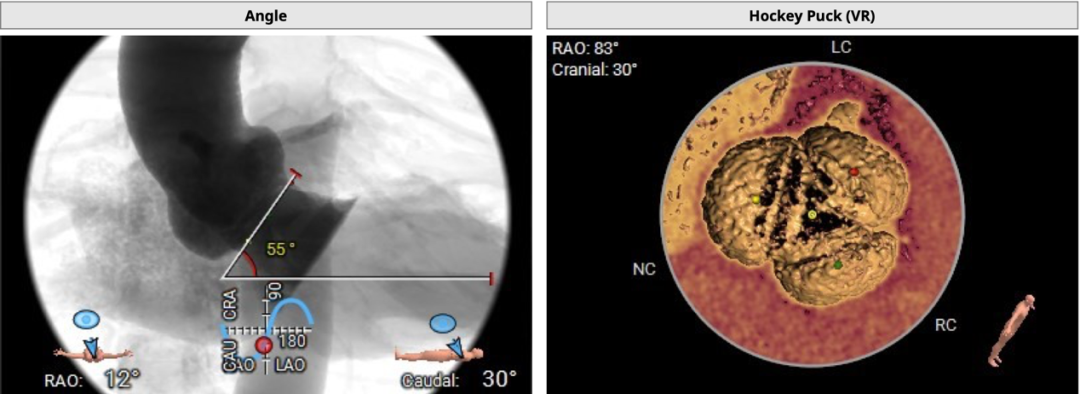

术中建议造影角度RAO:12°,CAU:30°:

心室角度55度:

29mm瓣膜模拟效果: